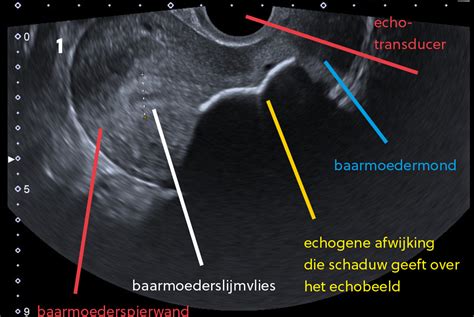

Als uw gynaecoloog vermoedt dat er sprake is van IUGR, zal er in het ziekenhuis een nauwkeurige echo worden gemaakt. Tijdens deze echo wordt niet alleen het gewicht van het kindje geschat, maar wordt ook een flowmeting (Doppler-meting) gedaan. Deze meting kijkt naar de bloeddoorstroming in de bloedvaten van de baby, waaronder in de navelstreng en in het hoofd.

De echoscopist zal ook letten op de verhoudingen tussen de verschillende lichaamsdelen van de baby. Is de buik van de baby in verhouding veel kleiner dan de benen en het hoofd? Dan is de kans groter dat de placenta onvoldoende werkt. Als de verhoudingen wel kloppen, maar de baby toch klein is, wordt de bloeddoorstroming gemeten.